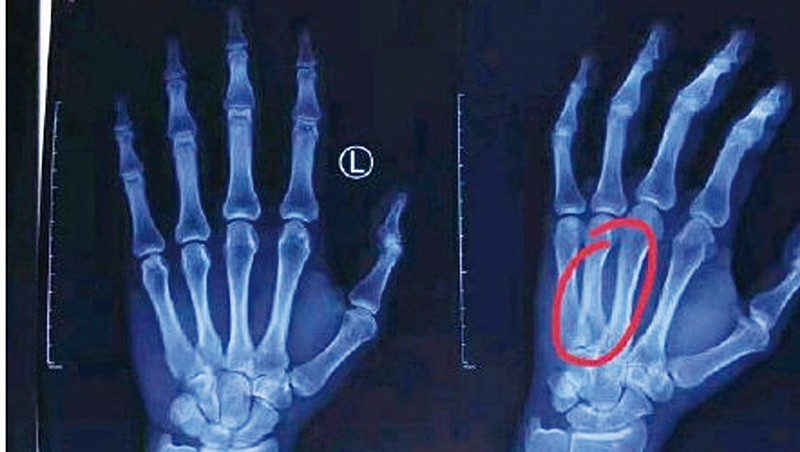

韩德君在比赛之后立刻就前往医院进行了检查,结果X光片显示,他的左手第四掌骨骨折。辽宁男篮昨天公布了韩德君的伤情和治疗方案,“韩德君这两天经过北京医院的专家会诊,确定为左手第四掌骨骨折,专家们根据大韩的病情给出了非常完善的治疗方案,大韩本人也同意了不手术、采取保守治疗的方案。至于大家非常关心的大韩何时能够康复并回到赛场的问题,医生并没有给出明确的时间,只是要求定期复查,根据恢复的具体情况确定何时能够复出。”据了解,保守治疗方案是在充分尊重球员本人意愿的情况下,最终采取的方案。

对于韩德君掌骨骨折这种伤病,只有两种治疗方案,一种是手术,另外一种就是保守治疗。如果进行手术,就需要在骨折的掌骨植入金属护具,并用螺丝进行固定。因为韩德君的骨折程度不算严重,并没有发生错位,可以采取保守治疗。手术治疗是很多未来要参加重大比赛球员,为了保证恢复后能够尽快进行训练、比赛而采取的治疗方法。而此次韩德君选择保守治疗,也就是用石膏将左手掌进行固定,依靠骨头的自然生长愈合,这样的方法会更稳妥一些,但不太利于短时间内复出。这也就意味着韩德君本赛季复出的可能性不太大,就算伤处能够自然长好,但如果贸然复出,造成二次受伤,真的是得不偿失。